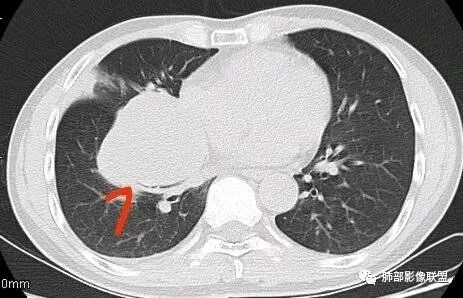

常规考虑:1、肉瘤首先考虑

2、胸膜孤立性纤维瘤待排

南边:结果:肉瘤

南边:病灶边界清,提示侵袭性弱,膨胀生长为主;这时候我们提示病灶不应该是支气管关系密切,提示间叶来源或胸膜来源

深分叶,警惕恶性